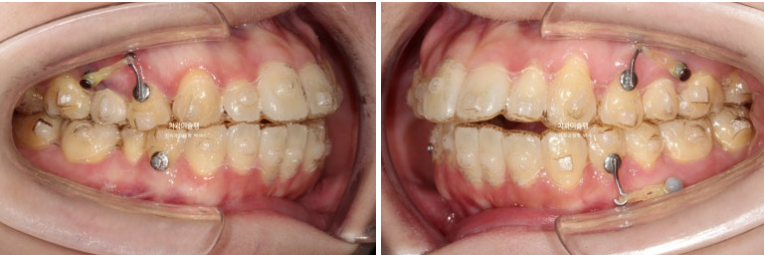

25.02

어금니를 뒤로 밀기위한 교정용 나사도 심고 진행합니다.

현재는 주로 뺐다 꼈다 하는 고무줄 처방을 하지만 환자분의 장치착용 협조도가 좋은 경우 치아에 직접 거는 고무로도 후방이동이 가능합니다.

어금니들이 사랑니 공간으로 순서대로 이동하며 공간이 생기는 중입니다.

안으로 쓰러졌던 작은어금니는 공간이 충분히 만들어 진 후 세우는 중입니다.